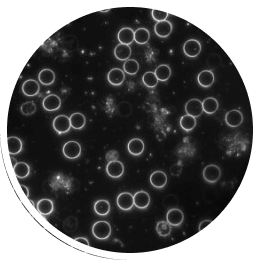

Tässä verinäytteessä on nähtävissä solukonglomeraatteja kolikkorullien muodossa. Tämä on tyypillinen merkki matalasta solukalvojännitteestä.

Tässä kuvassa on verinäyte samalta potilaalta vain 15 minuutin papimi -hoidon jälkeen.

©Prof. Dr. med. Thomas Rau